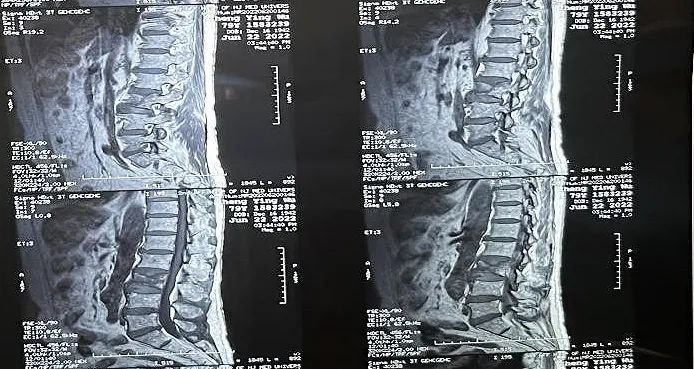

患者術前影像